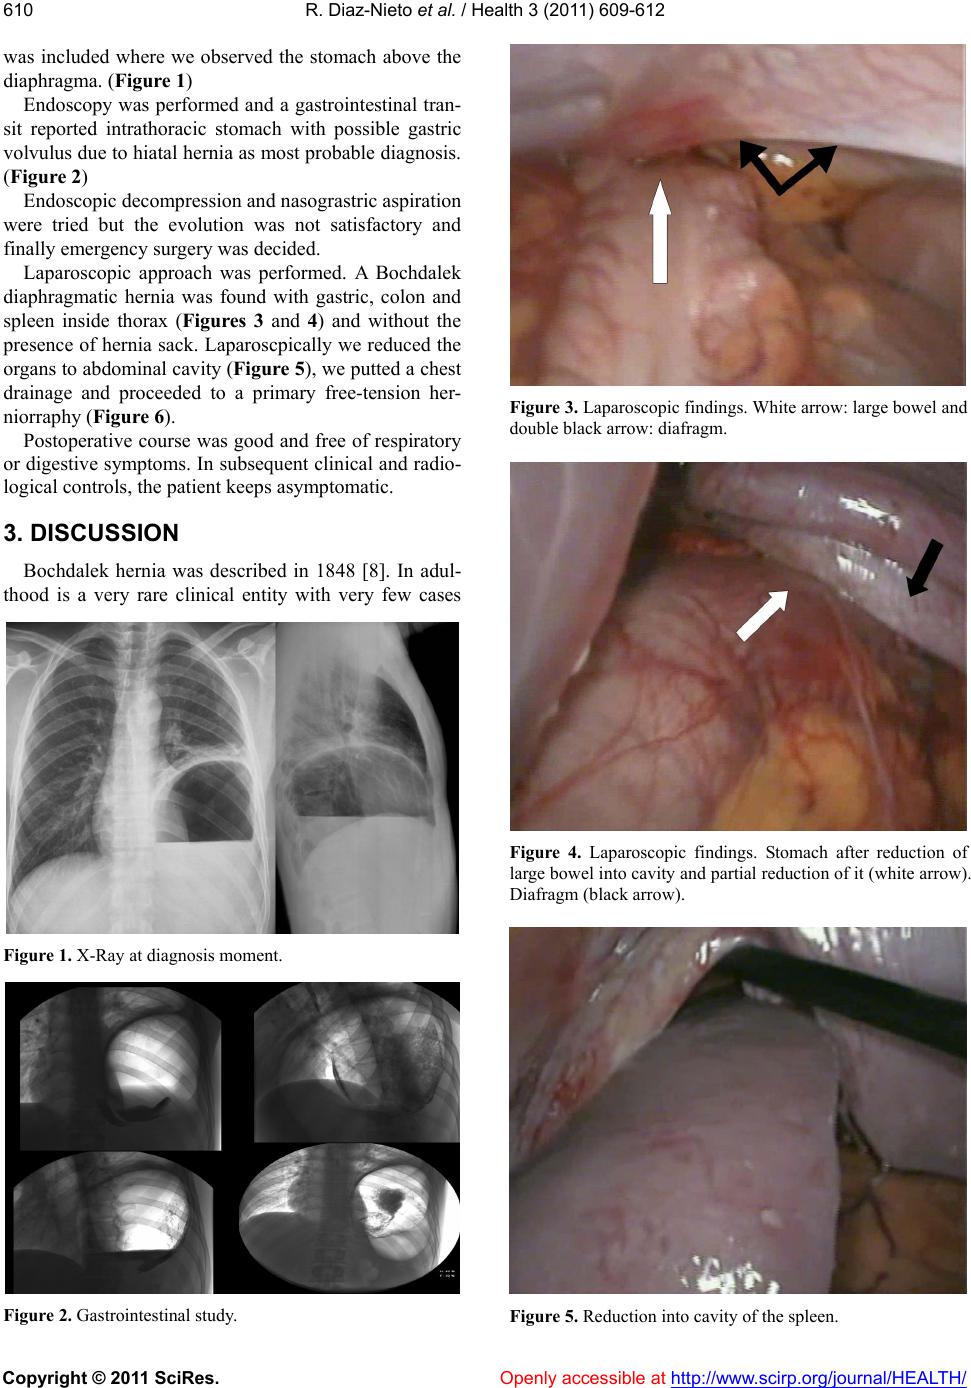

Figure 6. Primary stuture of diafragm.